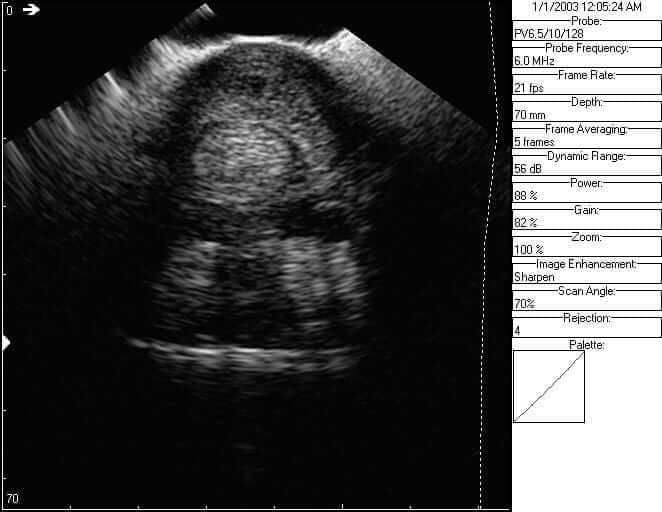

Here are some ultrasound images but in order to know abnormal, we first must know normal. The image to the left is of this horse’s normal left front tendon region, demonstrating normal anatomy and sizes of the flexor tendons just above the fetlock region. The white arrow demonstrates the superficial flexor tendon, which is a comma shaped structure, essentially overlapping or wrapping around the deep flexor tendon from the 11 o’clock to the 2 o’clock position. The deep flexor tendon, which is the yellow arrow, and a more circular type structure. Both tendons are viewed on cross section. There is a small black central area to the superficial flexor tendon here in the ‘normal’ leg, which may be a central area of injury that has occured in the left fore as well.

The image to the right is the same region on the right front, which is the injured limb. By comparing the two images, we can see that the superficial flexor tendon on the right fore is dramatically enlarged with a central black region, which is a core lesion. The overall enlargement is likely due to scarring or fibrosis within the tendon, but we can appreciate that the superfiical flexor tendon in the right front is so large that it is wrapping around the deep flexor from about the 10 o’clock to the 5 o’clock position.

If we measure the circumferance of the superficial flexor tendon on the right front, it is approximately 97.0 mm with the central core (black) lesion being about 19.9 mm.